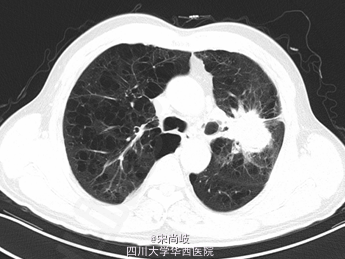

胸廓桶状,双肺呼吸音过清。胸部CT提示双肺慢支炎肺气肿表现,左肺上叶见4.9*4.0CM软组织肿块。

诊断为:左上肺包块。全麻下行剖胸探查+左肺上叶肿物取活检术,术中见胸内淡黄色积液50ml, 轻度粘连,胸膜有种植; 肿块位于肺门部及上下肺叶,约8*7*7cm大小,有脏层胸膜皱缩、有侵犯壁层胸膜;肿瘤距隆突<2cm,侵及纵隔胸膜,心包;淋巴结肿大及侵犯情况:7组,10组,11组淋巴结肿大,质硬,与周围组织紧密粘连;术中冰冻果:(左上肺肿物)倾向非小细胞型肺癌,术中特殊情况:左上肺肿物侵入左下肺及左肺门部,质硬,活动度差,周围淋巴结肿大,质硬,与肿物紧密粘连,无法分离。术中过程顺利,术中出血约50ml,术后安返,给予止痛,抗炎,化痰等治疗。